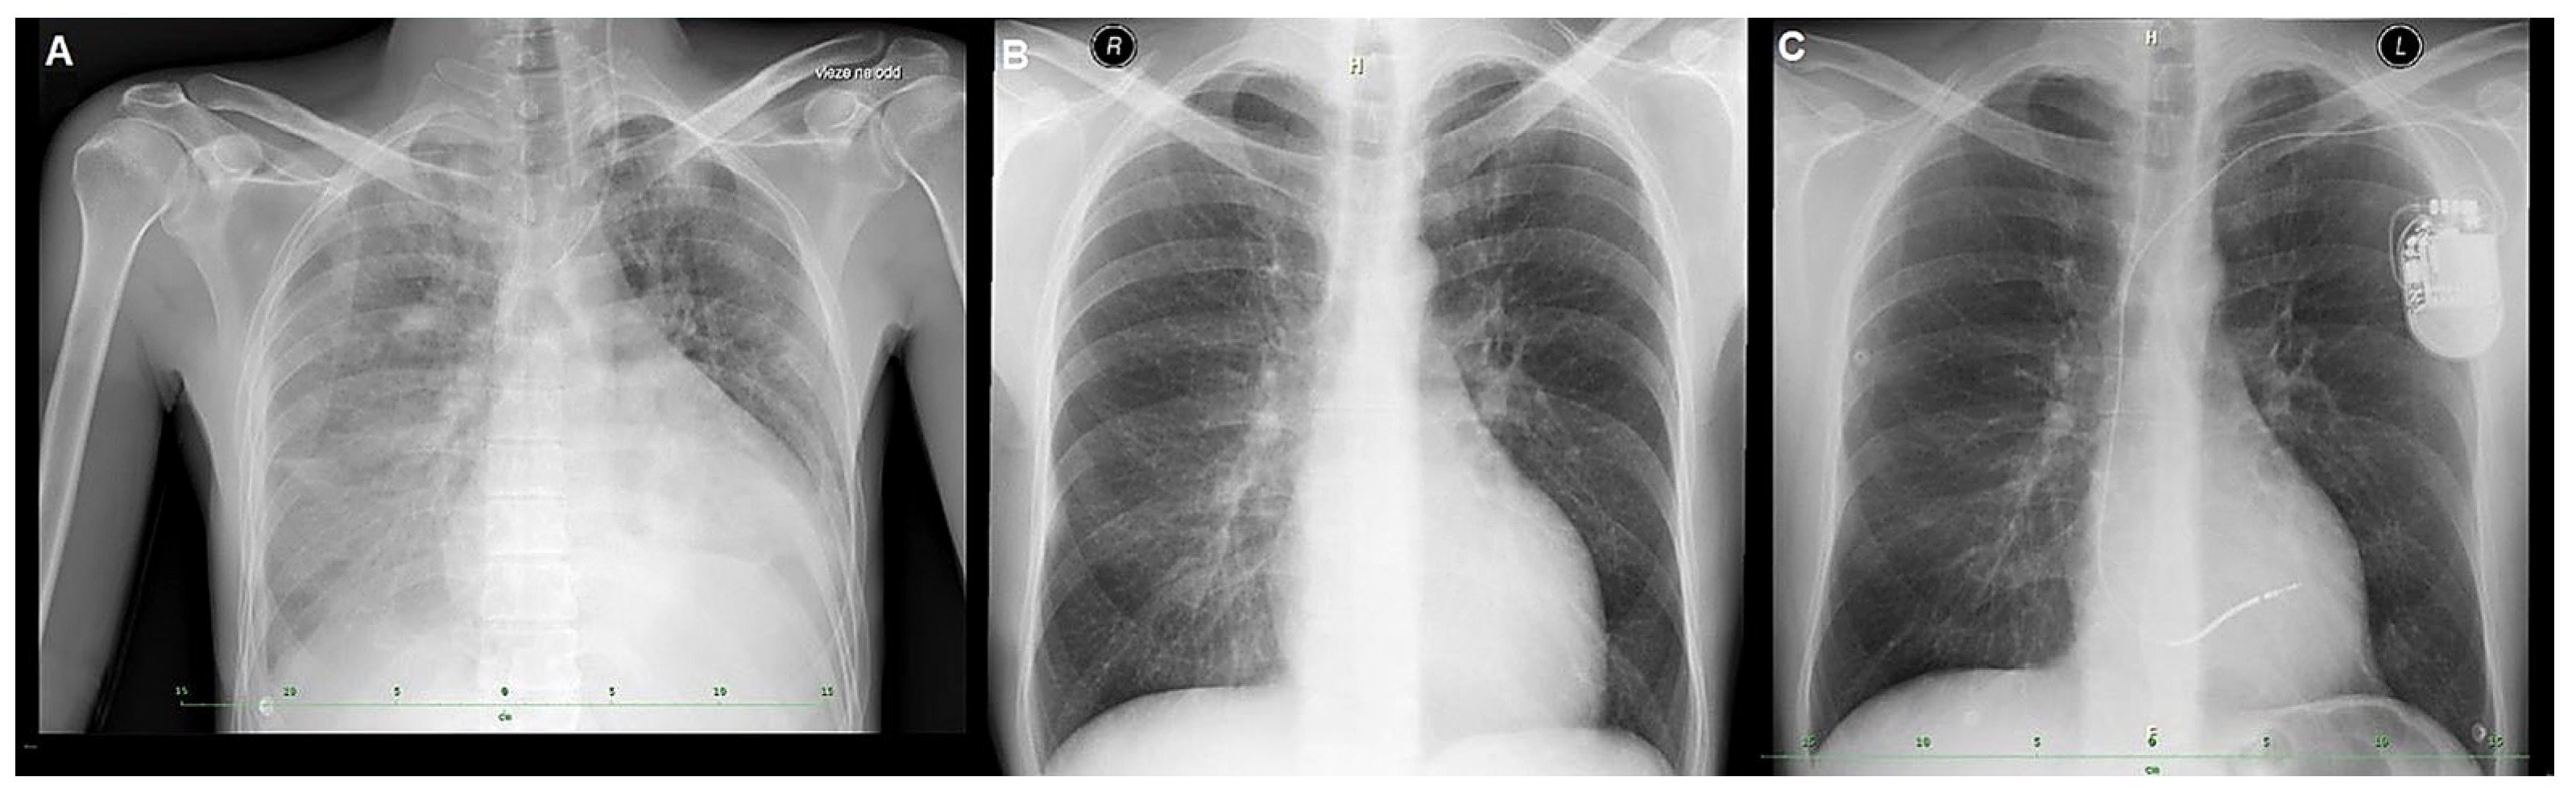

| Early hospitalization | LV hypertrophy + systolic dysfunction; pericardial effusion | TTE (details), CMR | Guideline-directed HF therapy as tolerated |

| SCD prevention | Advanced HF with narrow QRS | Device selection | Single-chamber ICD implanted |

| Advanced HF pathway | Persistent severe LV dysfunction | Multidisciplinary evaluation | Evaluated for HTx |